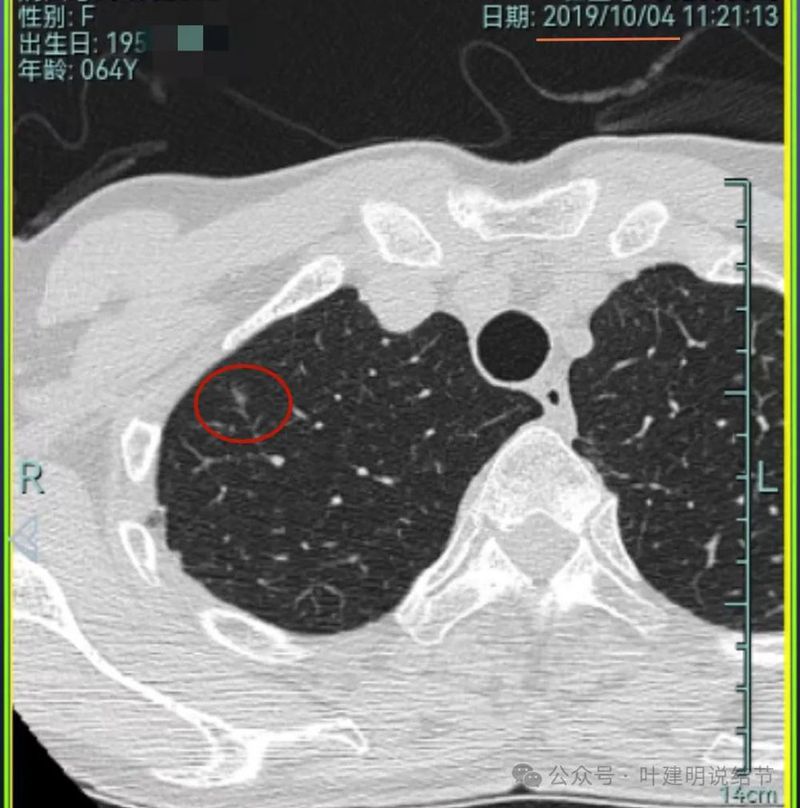

先来看2019年时的影像:

病灶1:右上叶磨玻璃密度结节,略偏长条状,有微小血管进入,轮廓与边界较清。

病灶2:右下叶磨玻璃结节,边缘不平毛糙,没有实性成分,轮廓与边界较清楚。